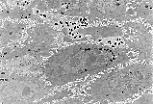

透射电镜(M.E.T.)下可清晰观察到角质形成细胞的基底突起。

角质形成细胞的侧面与相邻细胞紧密嵌合,这种结构增强了表皮的黏附性。 |

透射电镜下,比佐泽罗小体对应于富含桥粒和张力丝的区域。 | |

透射电镜观察颗粒层还可见:细胞膜增厚形成角化包膜,以及奥兰德小体。 | |

透射电镜下可见黑素细胞质内的黑素小体,这是高尔基复合体来源的结构, 黑色素的合成在此分多个阶段进行。 | |

高倍镜下可分辨黑素细胞的突起(富含黑素小体),这些突起穿插在角质形成细胞之间(可通过细胞质内的张力丝识别角质形成细胞)。

角质形成细胞也含有通过胞吐作用从黑素细胞获得的黑素小体。 |

透射电镜显示梅克尔细胞质内含有大量 神经内分泌颗粒 。 | |

透射电镜下, 朗格汉斯细胞可通过凹陷的细胞核、淡染且无张力丝和黑素小体的细胞质识别。

其细胞膜与邻近角质形成细胞之间无细胞连接(桥粒)。 |

透射电镜下识别朗格汉斯细胞的最佳方法是:在细胞质内找到特征性的球拍状小体——伯贝克颗粒。 | |